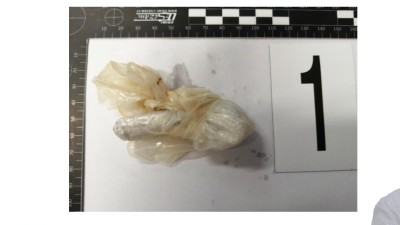

„K nehodě došlo 17. srpna mezi obcemi Patokryje a Lužice. Řidič osobního vozu předjížděl čtyři další auta. Náš kamarád Mára v tu chvíli jel na motorce a tento řidič jej srazil. Mára skončil s otevřenou zlomeninou, zdravotníci se snažili na poli najít kus kolene, aby mu tu nohu mohli dát dohromady. Po pár týdnech ale bylo jasné, že mu nohu musí vzít," popsala stručně tragický příběh Martina Vítková.